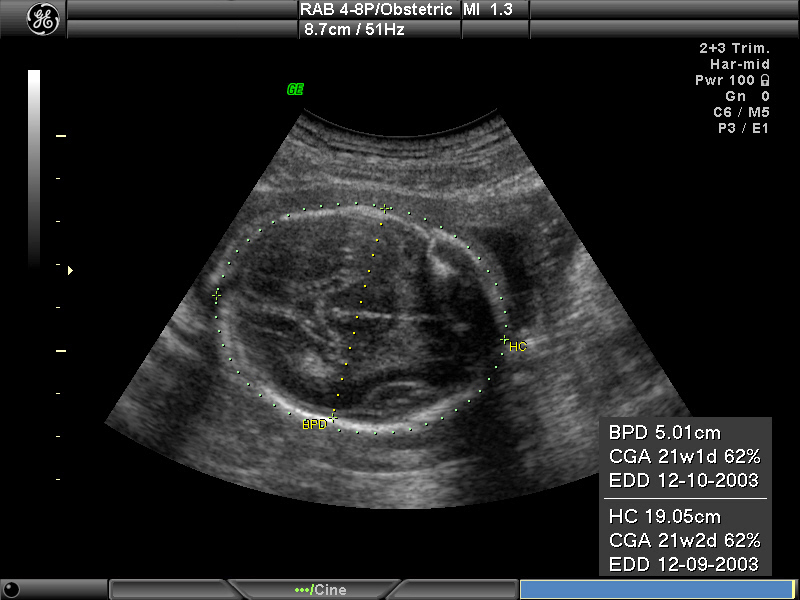

Chỉ số HC, hay chu vi vòng đầu (Head Circumference) của thai nhi, là một trong những chỉ số quan trọng trong siêu âm. Chỉ số này giúp bác sĩ xác định xem kích thước vòng đầu của trẻ có nằm trong giới hạn bình thường hay không. Chu vi vòng đầu đóng vai trò then chốt trong việc theo dõi sự phát triển của não bộ, chẩn đoán các bất thường liên quan đến não và hệ thần kinh, cũng như phát hiện những nguy cơ trong thai kỳ cho mẹ bầu.

Chỉ số HC cho biết kích thước vòng đầu thai nhi